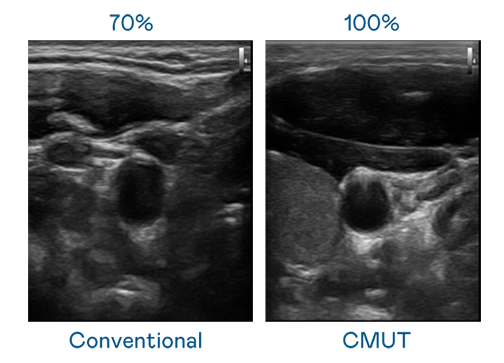

CMUT 技术是一种用电容式微机电元件来产生超音波讯号的技术。与传统 PZT 压电式技术相比,CMUT 频宽增加 30%,更宽频的超音波讯号让影像解析度大幅提升,是实现高影像品质医疗超音波扫描、促进精准医疗发展的关键技术。

大频宽带来超清晰影像

超音波影像的解析度高低,首先取决于探头能发出的讯号频宽。888电子 CMUT 可提供高清晰的超音波讯号,提供高频宽、高灵敏度、影像纹理细节更高的超音波影像,协助医护人员缩短影像判读时间及利用精准的医疗影像进行诊断。